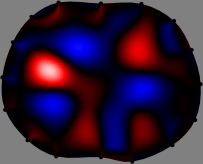

Figs. 3 and 4 compare the performance of the proposed FER method in (20) with the standard regularized least-squares method ((19) when \mathcal{R} is the identity matrix). The regularization parameter of the standard method was heuristically chosen for its best performance, and the parameter of the FER method was set to be one of three different values λ=0.05,0.2,𝜆0.050.2\lambda=0.05,0.2,\infty. The injection current was 1 mARMSRMS{}_{\tiny{\mbox{RMS}}} at 100 kHz, and the frame rate was 9 frames per second. The reference frame at t0subscript𝑡0t_{0} was obtained from the maximum expiration state. The measured data, 𝐕˙(tm)˙𝐕subscript𝑡𝑚\dot{\mathbf{V}}(t_{m}), represent the voltage differences between each time tmsubscript𝑡𝑚t_{m} and t0subscript𝑡0t_{0}. The blue regions, which denote where conductivity decreased by inhaled air, increased during inspiration and decreased during expiration. The FER method with λ=𝜆\lambda=\infty was clearly more robust than the standard method that produced more artifacts originated from the inversion process.

Figure 4: The reconstructed images of the conductivity change of the subject B by the standard regularized least square method and the proposed fidelity-embedded regularization (FER) method for three difference values λ=0.05,0.2,𝜆0.050.2\lambda=0.05,0.2,\infty. Here, the time step is 0.55 seconds (tm+5tm0.55subscript𝑡𝑚5subscript𝑡𝑚0.55t_{m+5}-t_{m}\approx 0.55).